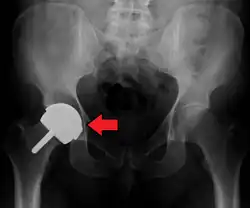

Dislocation

Dislocation (the ball coming out of the socket) is one of the most common complications. Hip prosthesis dislocation mostly occurs in the first three months after insertion, mainly because of incomplete scar formation and relaxed soft tissues.[19] The chance of this is diminished if less tissue is cut, if the cut tissue is repaired and if large diameter head balls are used.[21] Surgeons who perform more operations tend to have fewer dislocations. Important factors which are related to dislocation are: component positioning, preservation of the gluteal muscles and restoration of leg length and femoral offset.[22] Keeping the leg out of certain positions during the first few months after surgery further reduces risk.

Dislocations occurring between three months and five years after insertion usually occur due to malposition of the components, or dysfunction of nearby muscles.[19] Risk factors of late dislocation (after five years) mainly include:[19]